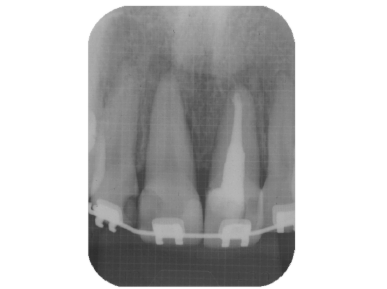

緊密な根管充塡

清潔な無菌的な根管の清掃が終了したら、緊密に根管充塡を行います。レントゲンで白く写る部分です。

根管治療の最後の処置です。根管の解剖学的な形態、彎曲度合い等によって数種類の根管充塡システムを当院では使い分けています。

また、最近はMTAセメントによる根管充塡も非常に予後がよく、取り入れています。